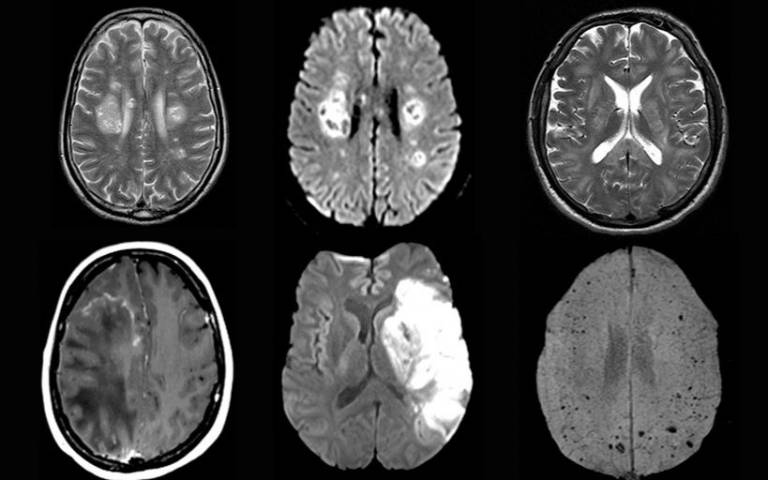

Фото: UCL

Коронавирус может привести к воспалению головного мозга, инсульту и повреждению нервов.

Они изучили протекание болезни у 43 человек в возрасте от 16 до 85 лет. У 10 из них была выявлена временная дисфункция мозга, а у 12 — его воспаления, некоторые из которых являлись острым диссеминированным энцефаломиелитом. Также наблюдались другие серьезные повреждения, например инсульты.

При этом у некоторых пациентов в исследовании не было серьезных респираторных симптомов, и неврологическое расстройство было основным проявлением COVID-19.

При этом вирус SARS-CoV-2, вызывающий COVID-19, не был обнаружен в мозговой жидкости ни у одного из протестированных пациентов. Это позволяет предположить, что вирус непосредственно не воздействовал на мозг, вызывая неврологическое заболевание. Необходимы дальнейшие исследования, чтобы определить, почему же у пациентов развивались эти осложнения.

У некоторых пациентов исследователи обнаружили указания на то, что воспаление мозга, вероятно, было вызвано иммунным ответом организма на заболевание.